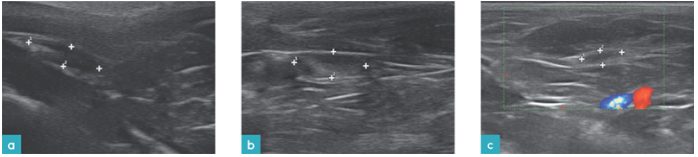

血管的超声影像为管状结构,由高回声外壁和无回声的内腔组成。浅表血管,尤其是静脉,易被探头所施的外力压塌。因此建议扫查这类血管时轻压即可。彩色多普勒或脉冲多普勒可用于区分浅表血管与其他结构。

神经的超声影像表现为低回声管状结构。神经的矢状面上可见两条高回声亮线,横截面则呈现为高回声亮线包围低回声组织形成的椭圆形或圆形结构(图10)。